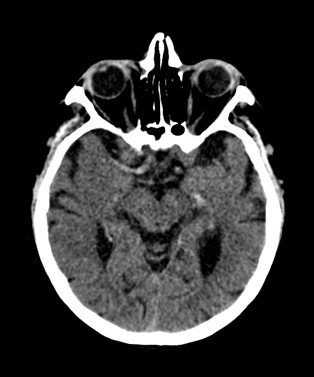

10.1.2.3. Computed Tomography (CT):_

It is an excellent and a widely available method for imaging the central nervous system.

It reliably depicts bony structures, calcifications and cerebrospinal fluid.

It is also capable to distinguish white matter from grey matter, as well as the CSF (0 HU) based on their density differences.

Fresh hemorrhage on CT appears hyperdense, therefore hemorrhagic stroke and subarachnoid bleeding can be promptly diagnosed with CT examinations.